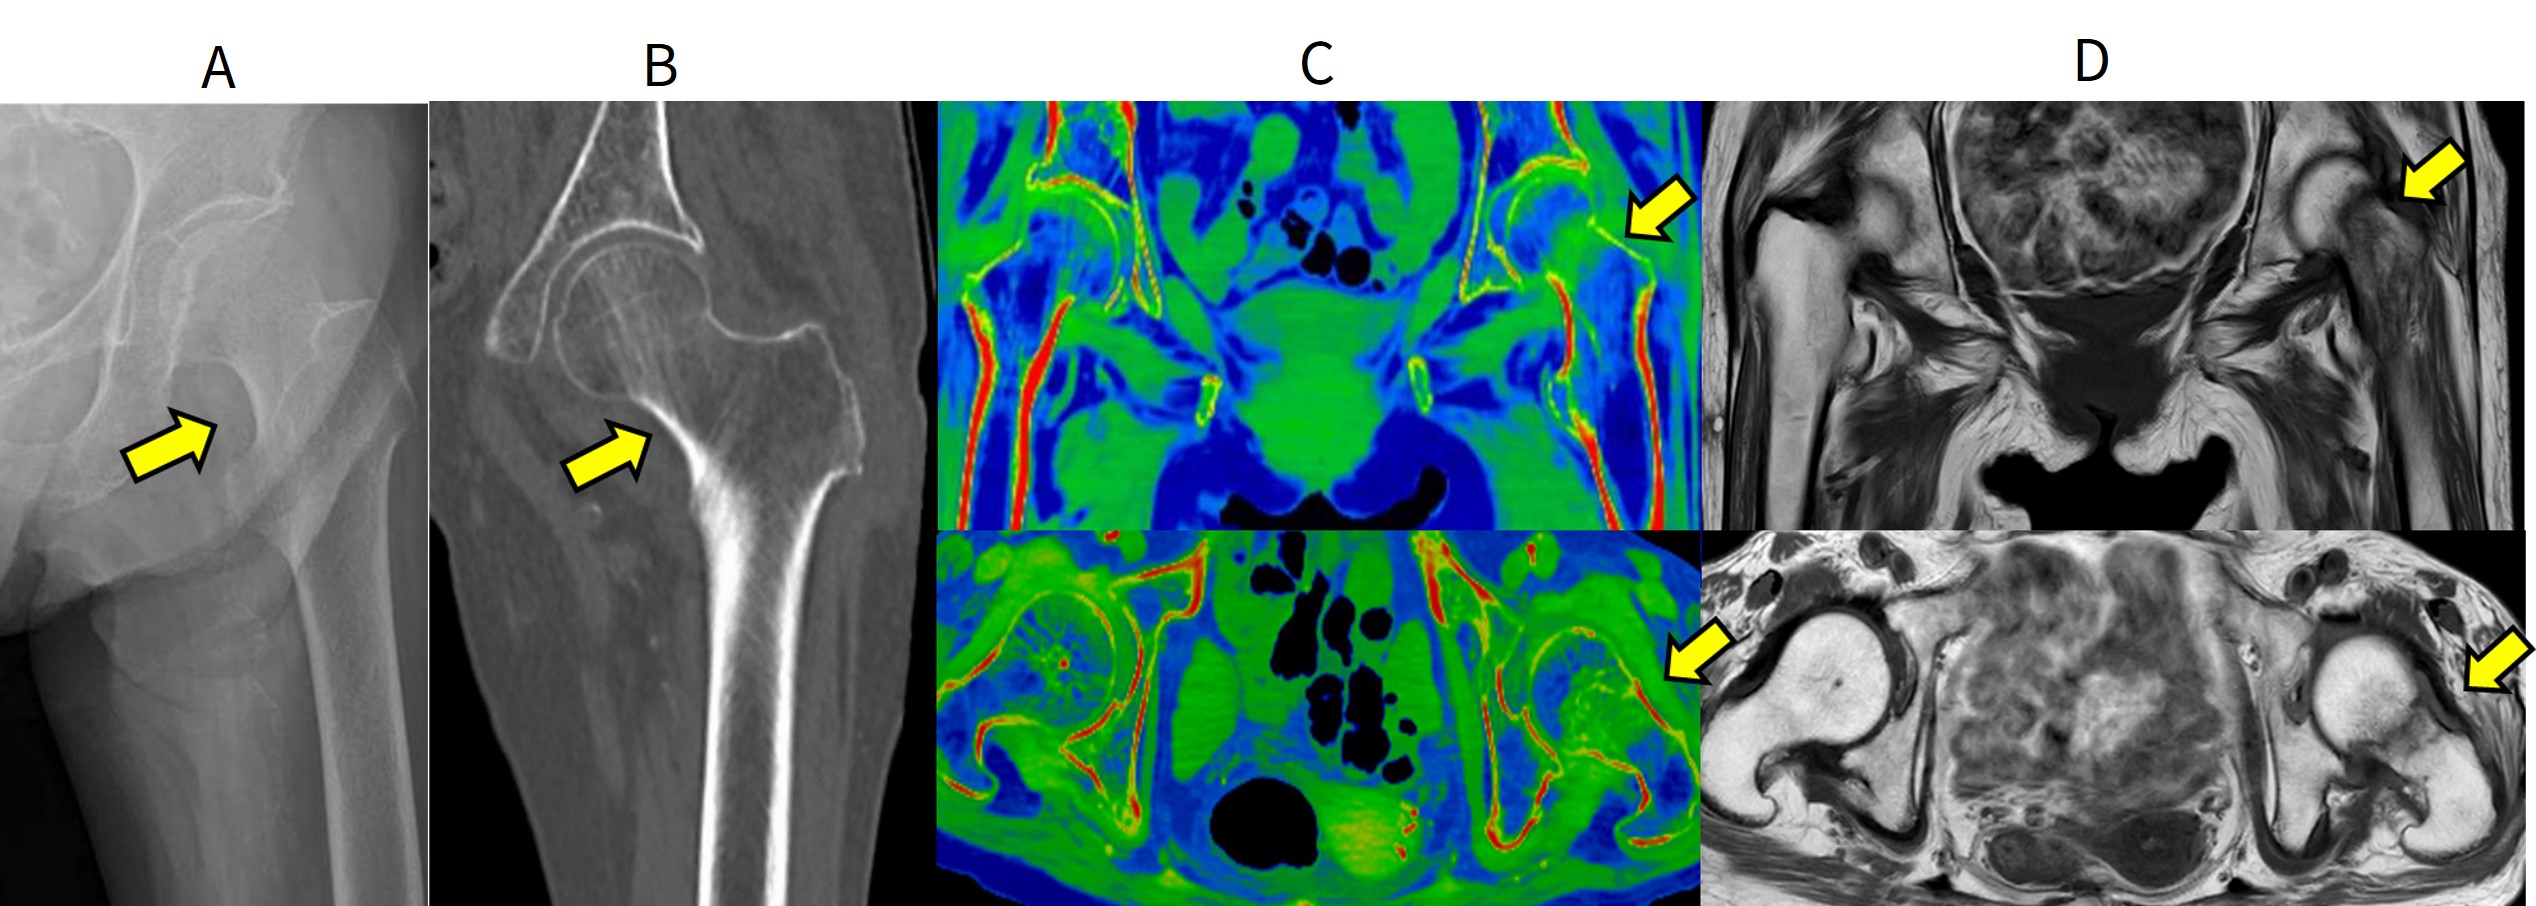

図1.右大腿骨転子部不顕性骨折

A.単純X線で大転子部に骨折が疑われる。

B.単純CTでは大転子骨折を認めるが、転子部には骨折線は認められない。

C.DECT像では転子部内側方向へ至る骨髄浮腫像(緑色の領域)を認める。

D.MRI(T1強調像)で転子部内側へ深達する骨折線を認める。